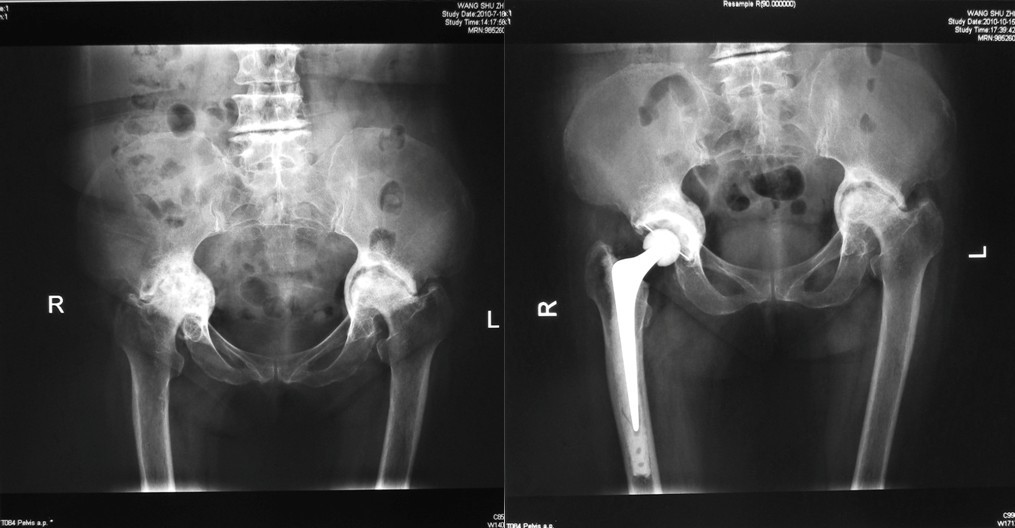

⑴Ⅰ型缺损:髋臼发育不良合并骨性关节炎,髋臼上缘Ⅰ型骨缺损,以金属网包含上缘缺损螺钉固定后,打压植骨,三代骨水泥技术全髋关节置换。

⑵Ⅱ型缺损:类风湿性关节炎合并髋臼内陷,髋臼缘完好。行颗粒骨打压植骨,三代骨水泥技术髋关节置换。

⑶Ⅲ型缺损:右髋关节置换术后骨溶解、假体无菌性松动造成髋臼巨大Ⅲ型骨缺损,行翻修术,以金属网包含髋臼上缘及髋臼内壁后,打压植骨,三代骨水泥技术全髋关节置换。